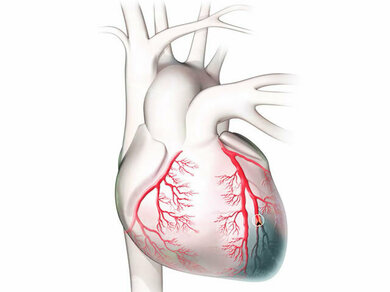

Ein Herzinfarkt wird durch den Verschluss eines Herzkranzgefäßes verursacht. In der Folge steigt der GOT-Wert

© W&B/Szczesny